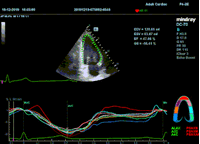

Всё изменилось с появлением технологии Speckle-tracking. Ультразвуковые приборы компании Mindray DC 8, 70, 80, Resona 6,7 оснащены данной функцией. Для использования необходим ЭКГ-канал. В чем же смысл данного технологического новшества? Прибор использует видео петли сечений миокарда, разбивает миокард на точки со стабильной визуализацией – speckle, и затем производит слежение каждой точки в течении нескольких сердечных циклов. Изменение пространства между точками дает нам представление о возможностях деформации миокарда, как продольной – Longitudinal Strain, так и деформации скручивания – торсии и Radial Strain.

На сегодняшний день в мировой клинической практике используется продольный Strain. Методика позволяет выявить нарушения в работе миокарда в каждом отдельном сегменте в среднем до 5 лет раньше клинического манифеста. Так же есть возможность оценки и диастолической функции, с гораздо более высокой чувствительностью чем тканевой допплер. Возможности радиального стрейна изучаются, за этой методикой будущее.

Как работать с данным методом? Для Longitudinal Strain необходимо записать видео петли апикальных сечений в память прибора: 4С, 3С, 2С. Для повышения качества трекинга рекомендуется производить запись на выдохе пациента. Затем произвести разметку по линии эпикарда, перикарда и центра миокарда. Нажатием кнопки «начать слежение» активируется программный алгоритм, видео петля оживает вместе с размеченными точками-speckle’ами. При необходимости производится коррекция. После анализа всех трех сечений можно получить данных продольной деформации как в среднем значении, так и по каждому сегменту миокарда левого желудочка. Нормальным показателем считается Longitudinal Strain -20%. Нижней границей -14%.

Видео примеры на приборе Mindray DC 70